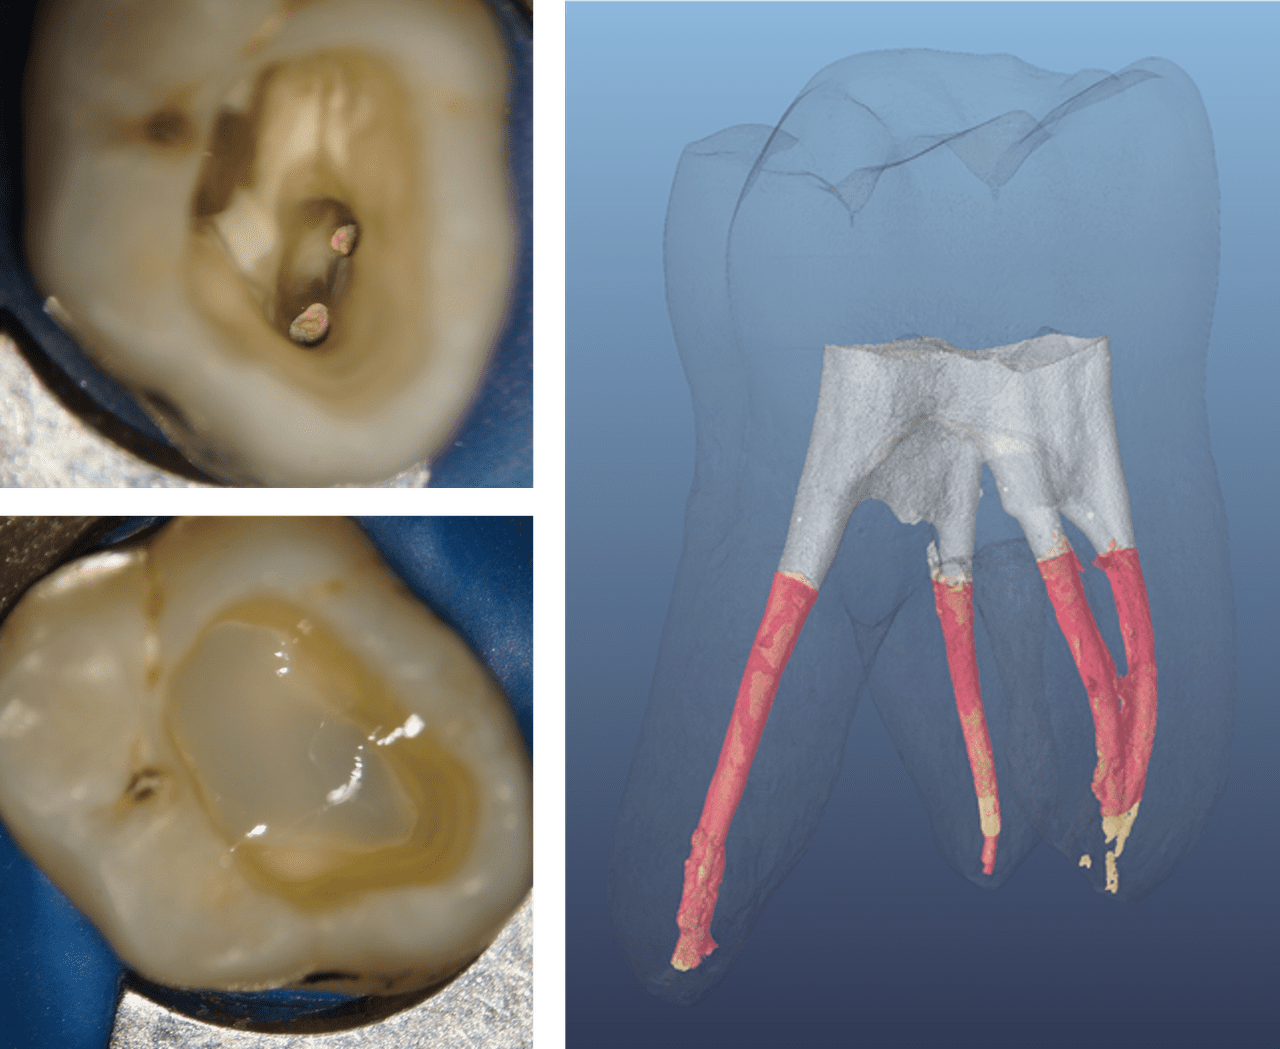

Şekil 2: Dört ve üç koronal duvarlı endodontik olarak tedavi edilmiş posterior dişler ve direkt restorasyondan önce ve sonra kalan diş yapısının çok az zarar görmesi

(Dr. Marcus Holzmeier’ın izniyle, Almanya)

Sonuç, Şekil 4'teki mikro-BT görüntüsünde gösterildiği gibi, ilk SDR® Pus kompozit katmanının post-endodontik Sınıf I kavitede adaptasyonunu gösteren sıkı bir şekilde kapatılmış koronal restorasyondur. SDR® Plus Bulk Fill Flowable, uygun bir koronal sızdırmazlık elde etmek için ideal koşulları oluşturarak hem kavite duvarlarına hem de kök kanalı obtürasyon malzemesine sorunsuz bir şekilde adapte olmuştur.

Şekil 4: Başlangıç SDR® Plus kompozit katmanının bir mikro-BT kullanılarak post-endodontik Sınıf I kavitede analizi.

SDR® Plus kompozit tabaka (gri), boşluk duvarlarına sıkı bir sızdırmazlık ve obtürasyon malzemesine (kırmızı) mükemmel bir uyum gösterir. (Görüntü kaynağı: Paqué F., 2014 (ref. 14.1483))